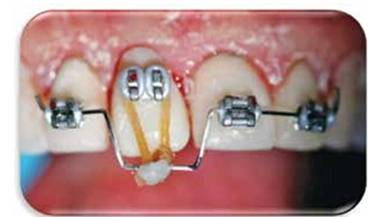

Se coloca una corona temporal de policarboxilato y se cementa.Se colocan brackets y un alambre de nitinol con un doblés a nivel de 1.1 para realizar tracción. (Figura 9)

Siete días después se observa un desplazamiento de la pieza hacia incisal junto el margen gingival. (Figuras 10A y 10B)

Figura 9:  Se colocan brackets y un alambre rectangular de 17 x 25 de nitinol con un doblés a nivel de 1.1 para realizar tracción coronal.

Figura 10A: Se señala ubicación del margen gingival.

Figura 10B: Control radiográfico donde se observa el alambre intraconducto haciendo función temporal de poste.

Figura 11: Control un mes después Nótese la extrusión de aproximadamente 2 mm a nivel incisal .